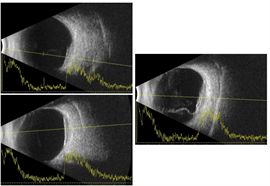

Spectral-domain optical coherence tomography (OCT) showed choroidal elevations with subretinal fluid OD and large choroidal elevation with intraretinal and subretinal fluid OS (Figure 2). Fluorescein angiography (FA) demonstrated two circumscribed areas of punctate hyperfluorescent spots located just above the superior arcade and nasal to the nerve OD and a large circumscribed area of punctate hyperfluorescent spots in the macula with central hypofluorescence OS (Figure 3). A/B scan ultrasonography shows two distinct choroidal hyperechoic lesions with high internal reflectivity in OD with maximal height of 2.90 mm and 2.50 mm and a choroidal hyperechoic lesion with high internal reflectivity with maximal height of 2.97 mm and associated subretinal fluid (Figure 4).

| Figure 3 | Figure 4 |